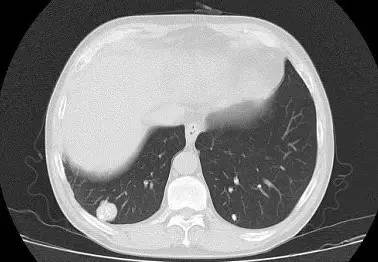

男,52岁,查体发现肺部病变

[影像描述]

右肺下叶结节样病变,内有钙化、脂肪成分,增强后可见轻度强化。

[检查结果]

右肺下叶错构瘤.

右肺下叶病变内有钙化、脂肪成分,典型爆米花样钙化,增强后可见轻度强化。